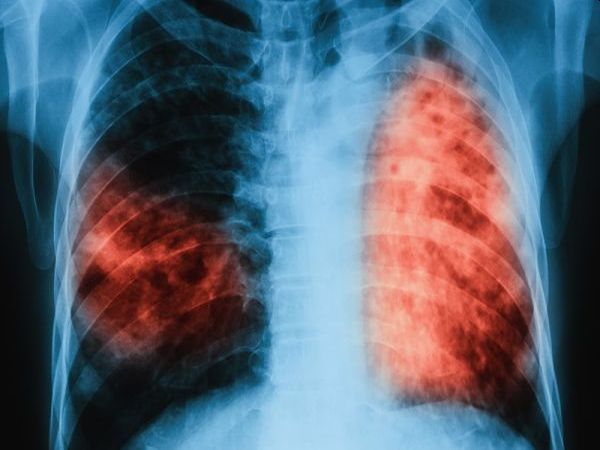

... лечение на туберкулоза, здравни медиатори, Български Червен кръст и общините. Туберкулозата е лечима и предотвратима, стига да бъде открита навреме и да бъде проведено качествено лечение.

...... 2013 г. до 13.5 на 100 хил. през 2023 г. Туберкулозата е лечима и предотвратима, стига да бъде открита навреме и да бъде проведено качествено лечение.

...... 2013 г. до 13.5 на 100 хил. през 2023 г.Туберкулозата е лечима и предотвратима, стига да бъде открита навреме и да бъде проведено качествено лечение.

...... 100 000 през 2023 г. Туберкулозата е лечима и предотвратима, стига да бъде открита навреме и да бъде проведено качествено лечение, посочват от здравното министерство.

...... от туберкулоза са починали 1 млн. и 600 хил. души. Туберкулозата е определена като 13-ата водеща причина за смърт и втория водещ инфекциозен убиец след Covid-19.

...... от туберкулоза са починали 1 млн. и 600 хил. души.Туберкулозата е определена като 13-ата водеща причина за смърт и втория водещ инфекциозен убиец след Covid-19.